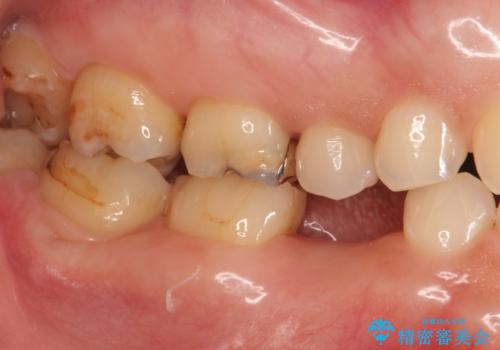

- 大人になっても残っていた乳歯が噛むと痛くなり、治療を求めて来院されました。

残す手段を検討しましたが大きな虫歯・根尖病変の存在し、大きく歯ぐきも腫れ炎症も強く認められる状態を改善するため抜歯を行いインプラントによる咬合機能回復を計画します。

大人になっても残っている乳歯は根管治療や他の治療で残せる場合もありますが、今回のように状態が悪い場合早期に抜歯をすることで歯槽骨が温存でき十分に安定した骨量でインプラントによる機能回復を達成することができました。